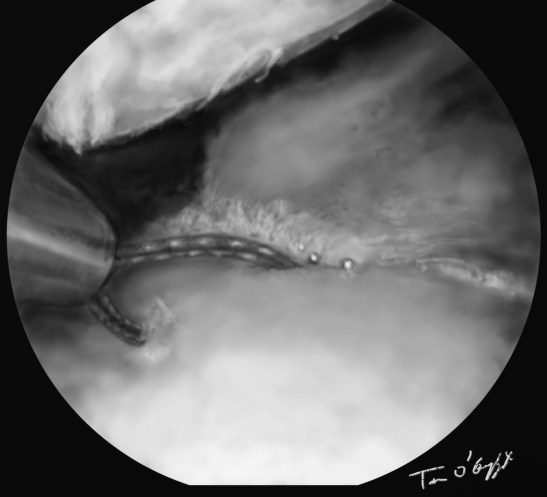

genou arthroscopie menisque suture

arthroscopie suture d’une fissure méniscale longitudinale